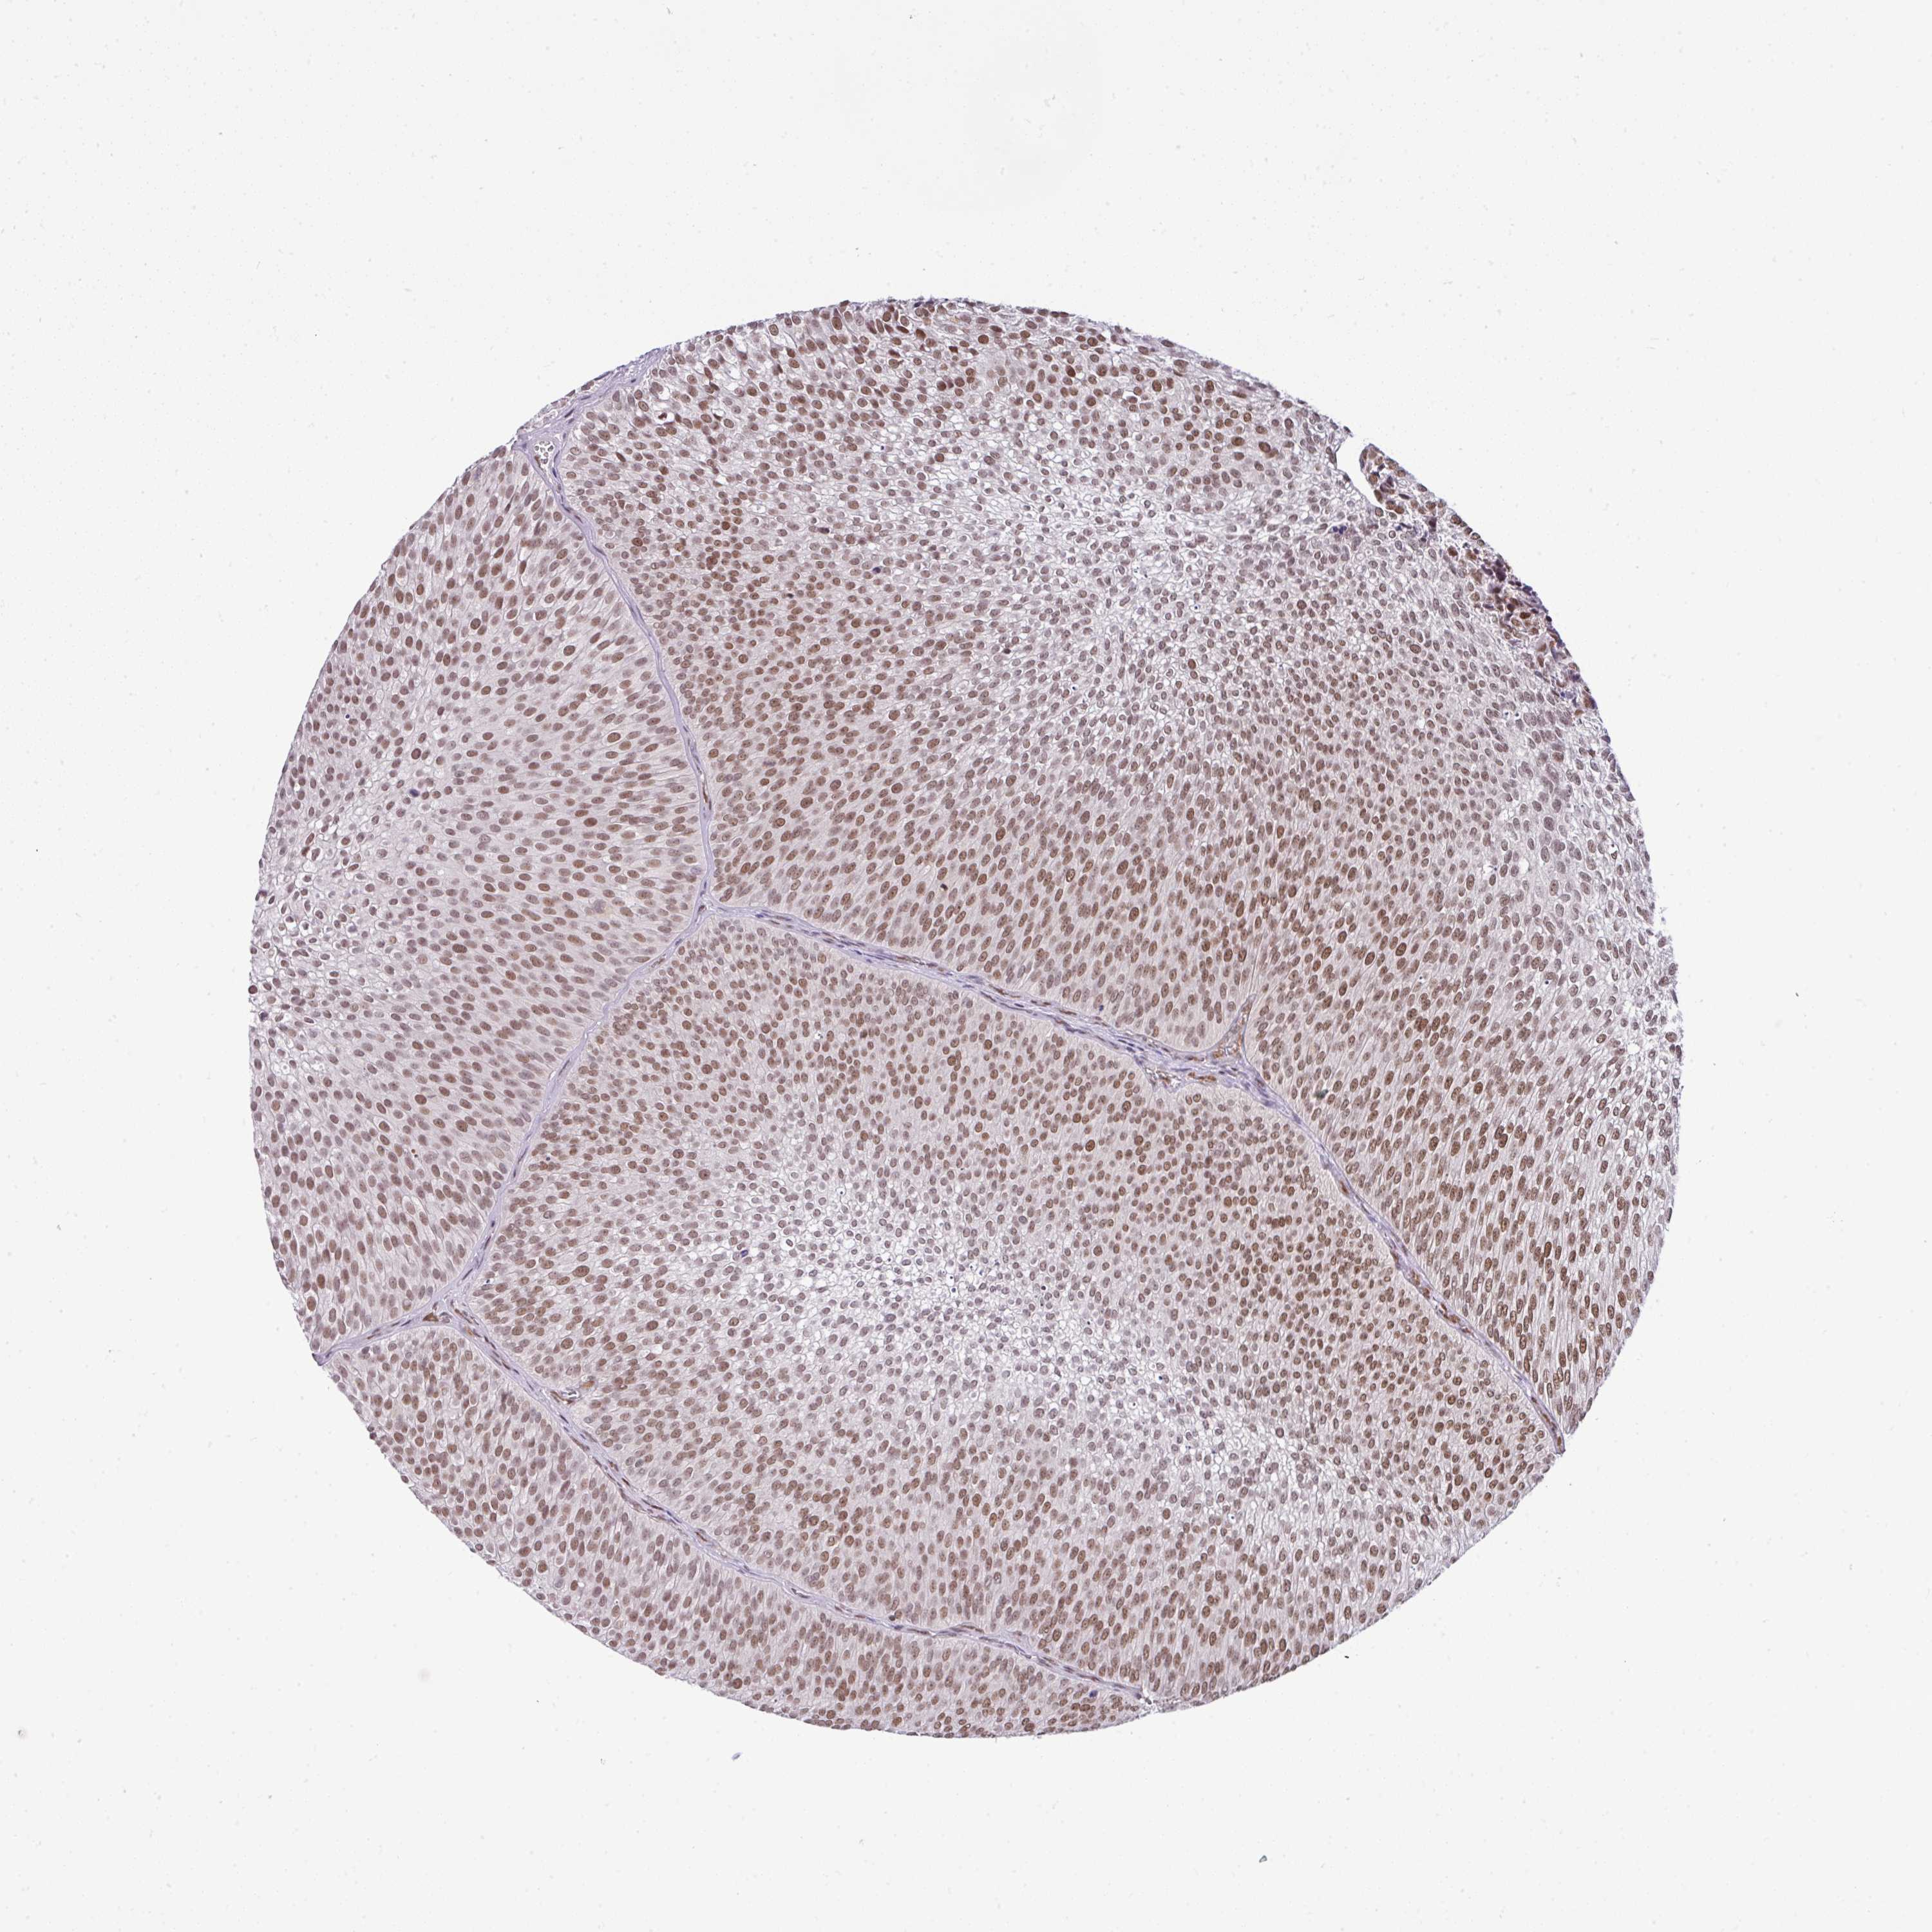

UROTHELIAL CANCER - Protein expressioni

A mouse-over function shows sample information and annotation data. Click on an image to view it in a full screen mode. Samples can be filtered based on level of antibody staining by selecting one or several of the following categories: high, medium, low and not detected. The assay and annotation is described here.

Note that samples used for immunohistochemistry by the Human Protein Atlas do not correspond to samples in the TCGA dataset.

Antibody stainingi

Antibody staining in the annotated cell types in the current human tissue is reported as not detected, low, medium, or high, based on conventional immunohistochemistry profiling in selected tissues. This score is based on the combination of the staining intensity and fraction of stained cells.

Each image is clickable and will lead to virtual microscopy that enables deeper exploration of all samples and also displays staining intensity scores, fraction scores and subcellular localization as well as patient and tissue information for each sample.

Antibody HPA011318

Antibody HPA054041

Staining

High

Medium

Low

Not detected

Intensity

Strong

Moderate

Weak

Negative

Quantity

>75%

75%-25%

<25%

None

Location

Nuclear

Cytoplasmic/membranous

Cytoplasmic/membranous,nuclear

Urothelial carcinoma, High grade

Urothelial carcinoma, NOS

Urothelial carcinoma, Low grade